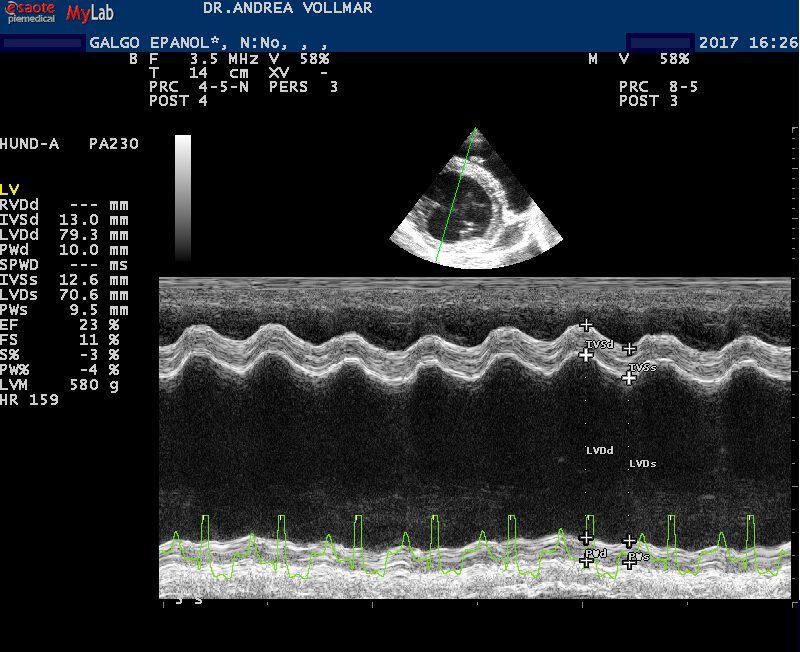

Dilatativen Kardiomyopathie (DCM)

Bei der dilatativen Kardiomyopathie (DCM) ist die Herangehensweise anders als bei MI. Die DCM tritt bei vielen größeren Hunderassen als Erberkrankung auf und unterscheidet sich bei verschiedenen Hunderassen in vielerlei Hinsicht, so auch im klinischen Erscheinungsbild und im Verlauf. Als auskultatorisch hinweisende Befunde kommen bei einigen Rassen zwar früh im Krankheitsverlauf Arrhythmien in Form von Extrasystolen oder Vorhofflimmern vor, häufig ist die Auskultation aber unauffällig. Leise Herzgeräusche entstehen erst spät im Krankheitsverlauf mit Entwicklung einer sekundären AV-Klappeninsuffizienz durch Dilatation des Anulus fibrosus und Papillarmuskelatrophie Daher basiert die Früherkennung allein auf der echokardiografischen Untersuchung, je nach Rasse ergänzt durch EKG-Befunde bis hin zum 24-Stunden Holter-EKG.

Besonders betroffene Rassen wie Dobermänner, Deutsche Doggen, Irische Wolfshunde, sollten ab dem jungen Erwachsenenalter regelmäßig kardiologisch untersucht werden - nicht nur aus zuchthygienischen Gründen, sondern auch, um dem Individuum möglichst lange eine gute Lebensqualität zu ermöglichen und die Lebenserwartung zu verbessern. Wie Erfahrungen aus der Humanmedizin und inzwischen mehrere veterinärmedizinische Studien zeigen, muss das vorrangige Ziel sein, die Erkrankung möglichst früh im präklinischen Stadium zu diagnostizieren und eine frühzeitige Therapie zu beginnen.

Bei Dobermann Pinschern wurde gezeigt, dass durch einen frühen Therapiebeginn mit Pimobendan die Zeit bis zum kongestiven Herzversagens oder plötzlichen Herztod gegenüber Plazebo um median 5,2 Monate und die Überlebenszeit um 9,2 Monate verlängert werden konnte. Bei Irischen Wolfshunden, bei denen die Erkrankung erst im späten Krankheitsstadium mit Stauungserscheinungen diagnostiziert und therapiert wurde, starben fast 90% der Hunde an der Herzerkrankung mit einer medianen Überlebenszeit von 7,3 Monaten, während Hunde mit Therapiebeginn im präklinischen Stadium der DCM median etwa 22 Monate (Hunde mit zusätzlich Vorhofflimmern) bzw. 29 Monate (Hunde mit DCM und Sinusrhythmus bei Erstdiagnose) überlebten und mehr als die Hälfte dann an nichtkardialen Todesursachen starb.